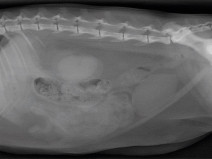

• Journée technique des GTV et AFVAC BFC (parcours Vétérinaire pour animaux de compagnie) : L'imagerie du thorax sous toutes ses formes

La radiographie reste un des principaux examens complémentaires de première intention en pneumologie.

L'espace d'une journée, nous vous proposons d'aborder les modalités d'une bonne réalisation et d'interprétation des radiographies du thorax. Nous nous attacherons également à analyser ensemble des images radiographiques normales et ano...